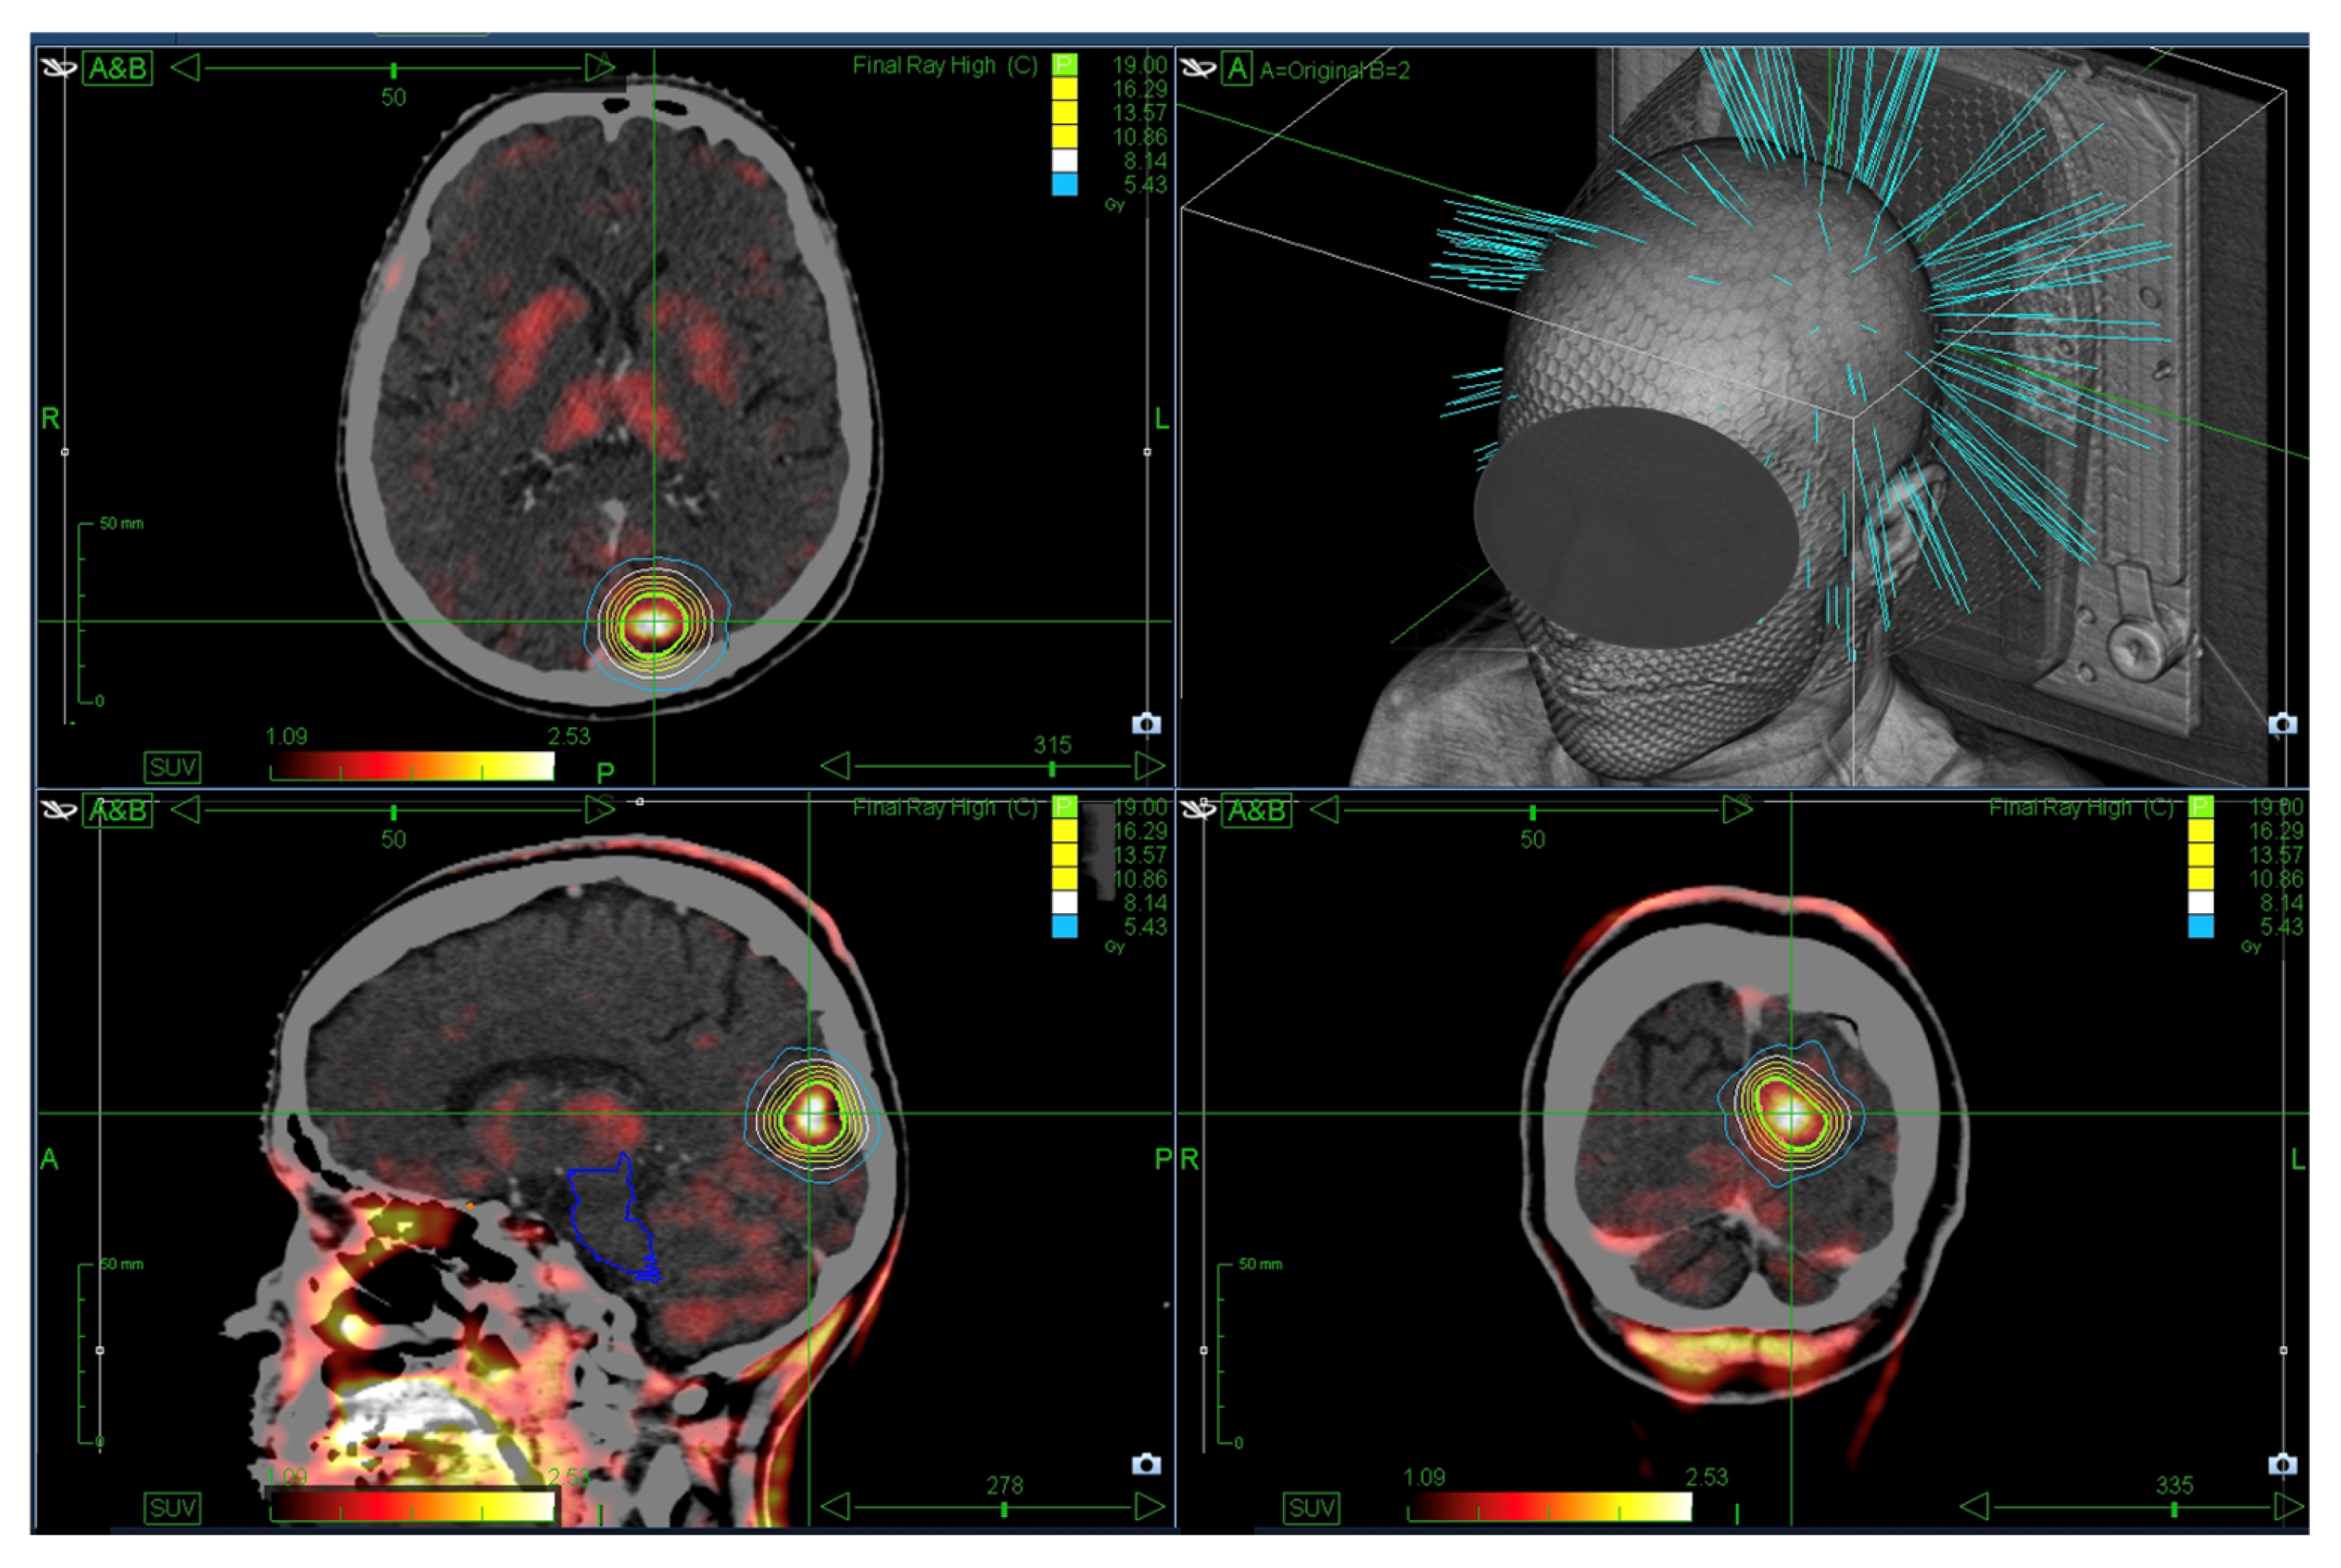

The gross tumor volume (GTV) was delineated using the most recent imaging, with a 0–2 mm margin to generate the planning target volume (PTV). Until June 2019, treatment planning was conducted using the MultiPlan (Accuray, Madison, WI, USA, versions 4.6.0 and 4.6.1) and subsequently with the Precision system (Accuray, Madison, WI, USA, versions 2.0.0.1, 2.0.1.1 and 3.2.0.0). Figure 1 displays an exemplary SRS treatment plan.

Figure 1.

Exemplary single-session SRS plan showing a prescription dose of 1 × 19 Gy (green) enclosing the PTV. The planning CT was fused with FET-PET for target definition.